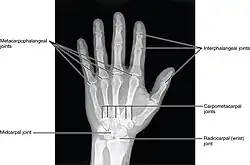

Articulations de la main, radiographie.